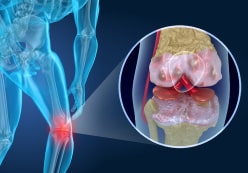

Lesioni

Come risultato di danni ai legamenti e alle ossa durante sport, attività o incidenti, si verifica un danno a uno o più componenti dell’articolazione.

borsite

Infiammazione della membrana sinoviale dovuta a infezioni e strofinamento eccessivo dell'articolazione durante il movimento.